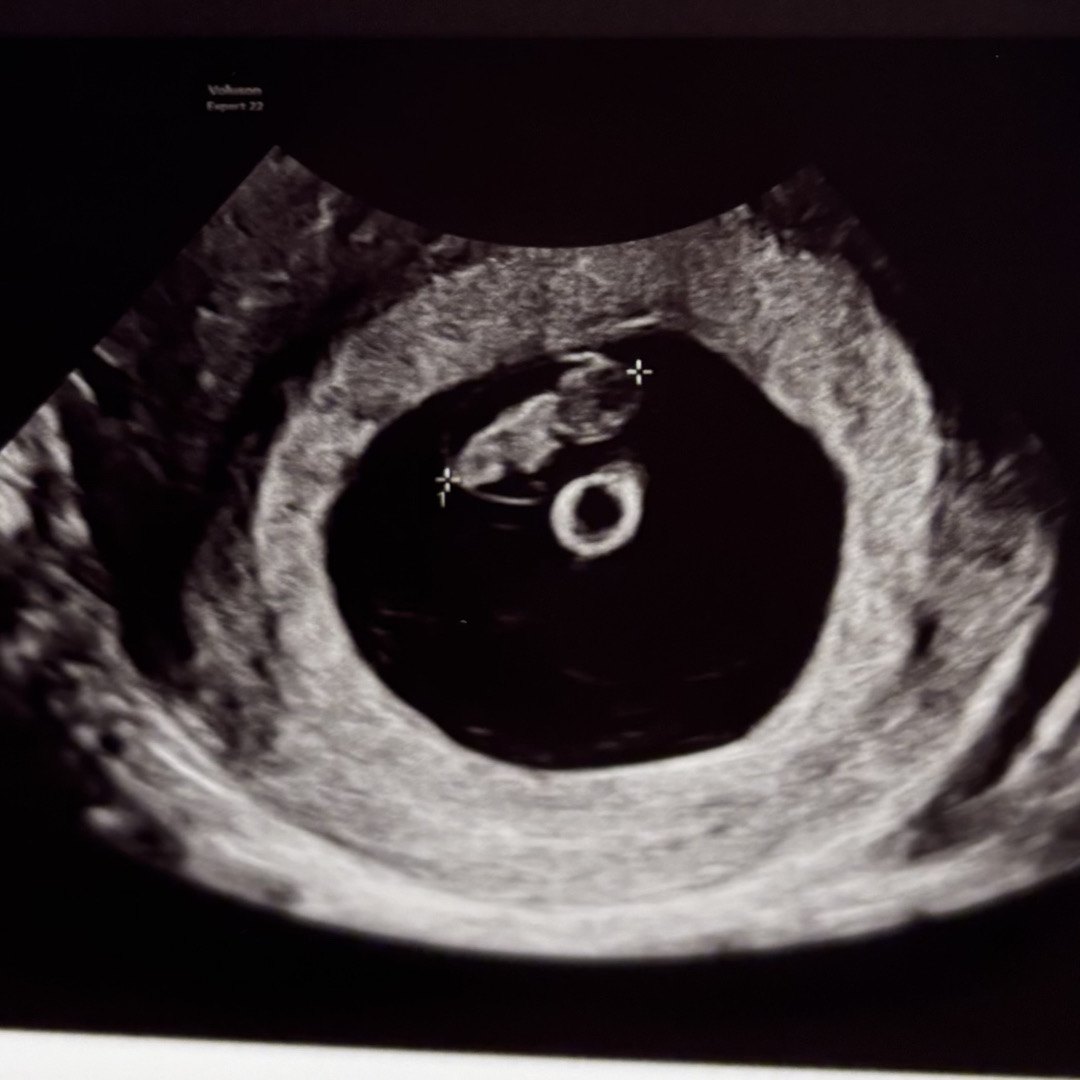

오늘 무사히 심소 들었어요💕

불안걱정핑이라 정말 걱정 많이했는데!! 정말 무사히 잘컸고 심장소리 잘들려주더라구요! 근데 기차소리도 말발굽소리도 아닌 쿵짝쿵짝 마치 덩기덕쿵더더럭해야할 장단이었어요💕 넘 웃겼어요 심소 들으러가기전이신분들도 다들 무사히 듣고오시길~~~7주 2일차였어요✨